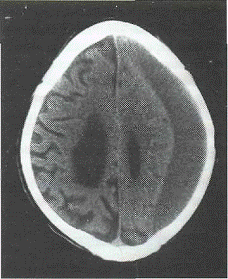

Семиотика. По плотности в единицах Haunsfild ХСГ делятся на

гиподенсивные (28 и менее Ед. Н), изоденсивные (29-45 Ед. Н), гиперденсивные

(более 45 Ед. Н) а также гетероденсивные (рис.4).

Рис.4. КТ варианты плотностных

характеристик ХСГ: а) гиподеисивыая; б) гипердепсивная; в) изоденсивная; г)

гетеро-дснсивная;